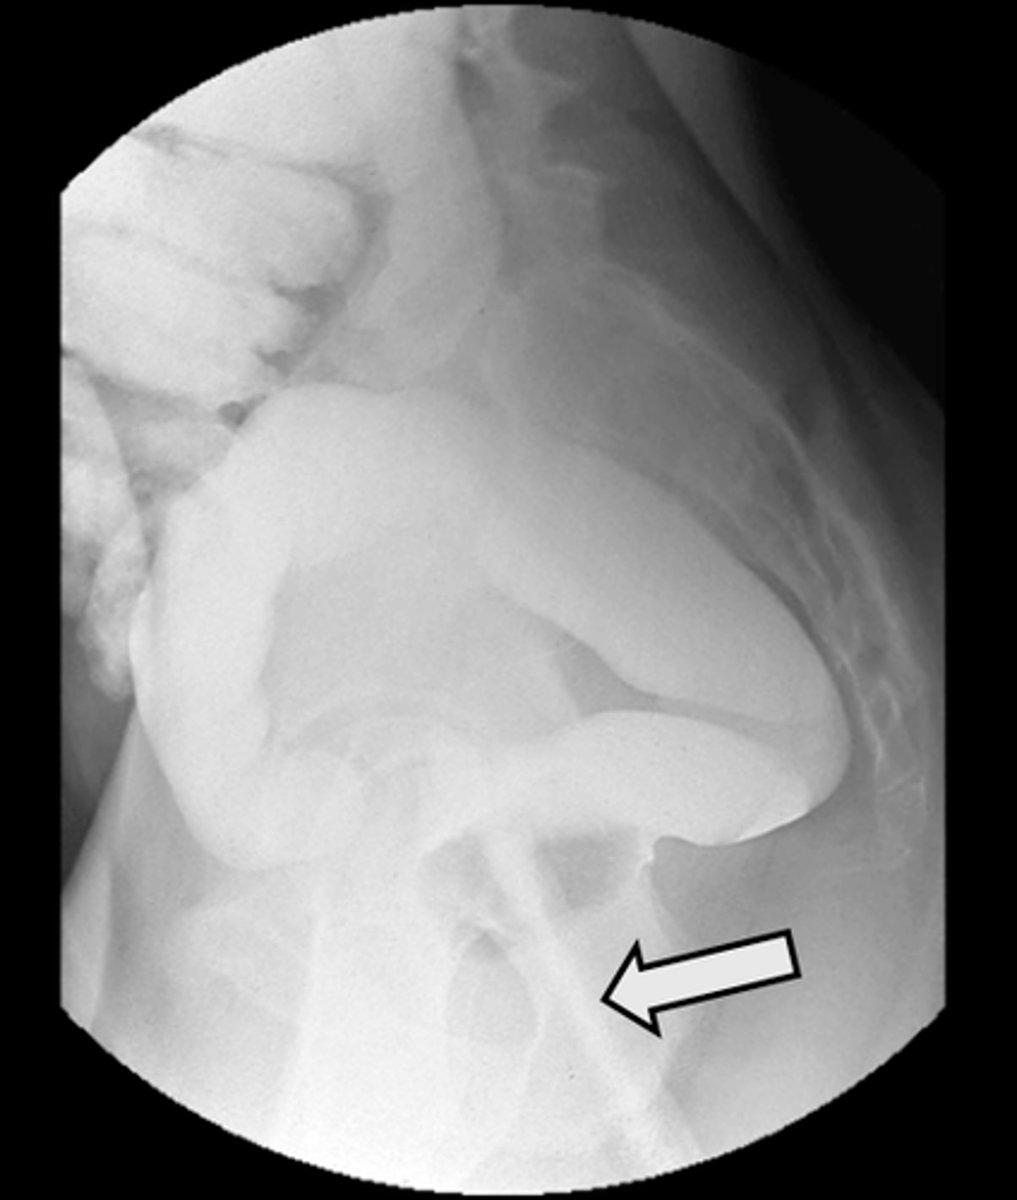

Lateral rectum with barium enema

What is the image?

47

Rectal tube

<p>What is indicated in the image?</p>

New cards

What is indicated in the image?